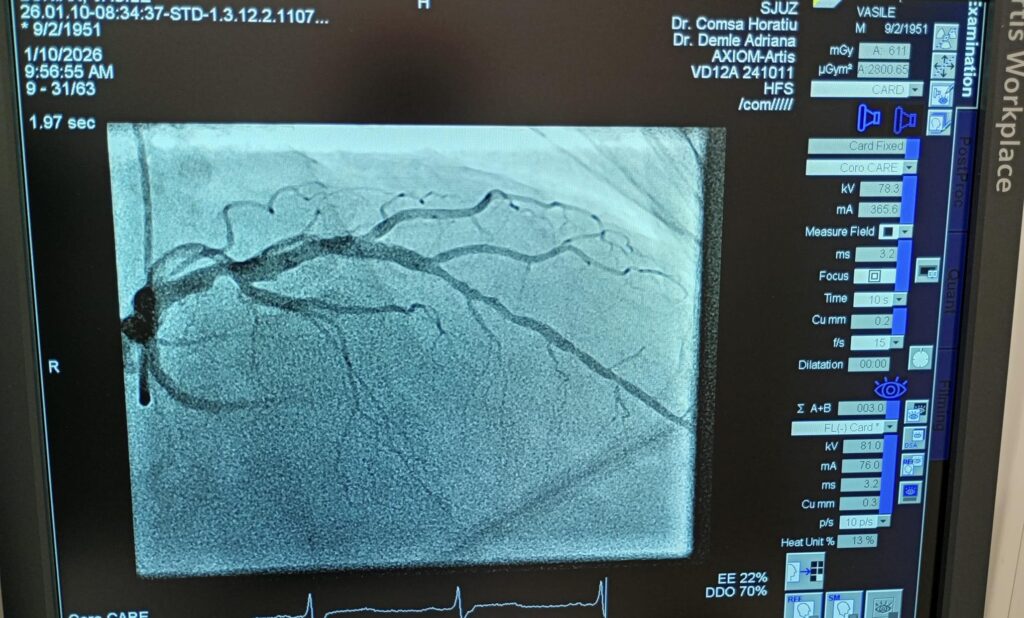

Spitalul Județean de Urgență Zalău marchează o nouă etapă importantă în dezvoltarea serviciilor medicale, odată cu realizarea primelor angiografii coronariene cu intervenții PCI și montare de stent, proceduri efectuate în premieră atât la nivelul unității medicale, cât și al județului Sălaj.

Procedurile au un rol atât diagnostic, cât și terapeutic, oferind pacienților cu afecțiuni vasculare coronariene posibilitatea de a fi investigați și tratați local, fără a mai fi nevoiți să se deplaseze în alte centre medicale din țară. Pentru bolnavii cardiaci, acest lucru înseamnă acces mai rapid la tratamente salvatoare și șanse mai mari de recuperare.

Primele cinci intervenții de acest tip au fost realizate cu succes de echipa Compartimentului de Cardiologie Intervențională, în colaborare cu specialiștii Secției de Anestezie și Terapie Intensivă, sub coordonarea medicului Horațiu Comșa. Reprezentanții spitalului au transmis mulțumiri și felicitări echipelor medicale implicate, pentru profesionalismul și rigoarea de care au dat dovadă.

După debutul programului de implantare a stimulatoarelor cardiace în cadrul Compartimentului de Cardiologie Intervențională, astăzi marcăm o nouă premieră pentru spital și pentru județul Sălaj: realizarea primelor angiografii coronariene cu intervenții PCI și montare de stent.

Aceste proceduri au rol diagnostic și terapeutic și reprezintă, pentru prima dată, posibilitatea ca pacienții cu afecțiuni vasculare coronariene să fie investigați și tratați local, în cadrul SJUZ, fără a mai fi nevoiți să se deplaseze în alte centre.